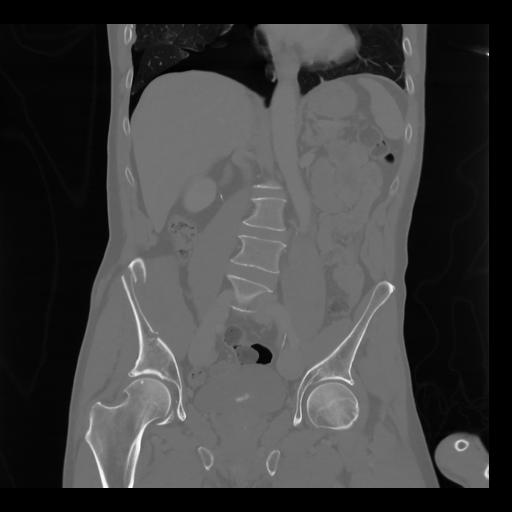

35 CUERPO,CE,Coronal,3.000,CUERPO,Coronal,